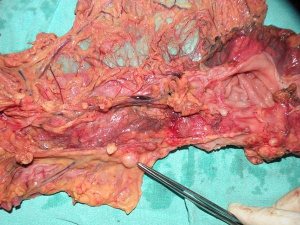

Extended right hemicolectomy 55 M from Dhanaula, with h/o anaemia, occult blood in stools positive and CT showing a mass in right colon. At operation, the cut section of specimen showed no real tumour inside but instead 3 strictures and multiple lymph nodes in mesocolon.Biopsy reported as eosinophilic colitis!!.